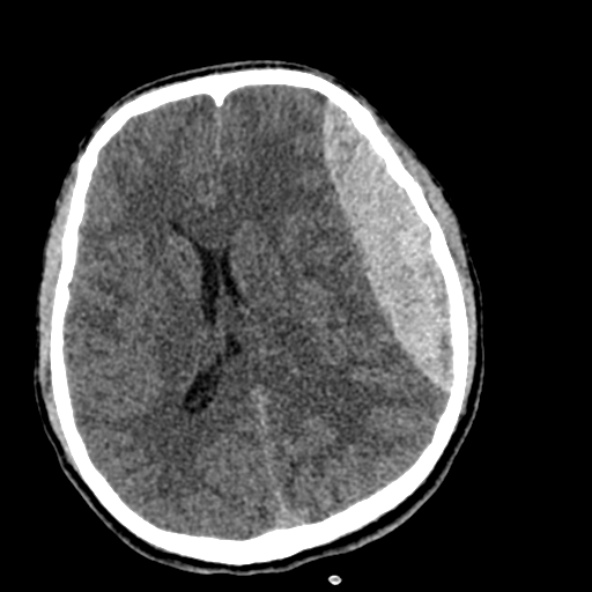

Puzzle 53 annotated

What's the Diagnosis?